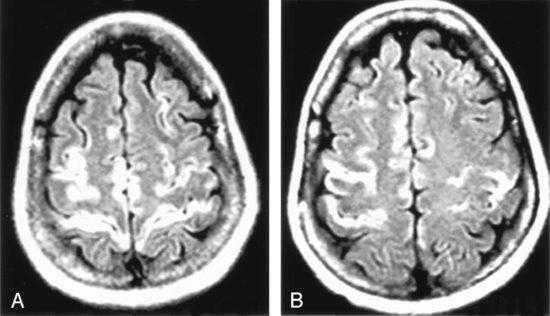

Рисунок 1 | Асимметричные области патологически повышенного МР сигнала в медиальных отделах обеих височных долей, больше выраженные в корковом веществе

Рисунок 2 | В последовательности DWI у того же пациента определяются области повышения сигнала в обоих лобно-височных областях. ИДК подтвердила ограничение диффузии

Т1-взвешенное корональное изображение после введения контраста демонстрирует асимметричное двустороннее гириформное и лептоменингальное контрастное усиление больше в области коры островка (большие стрелки) и поясной извилины (меньшая стрелка)